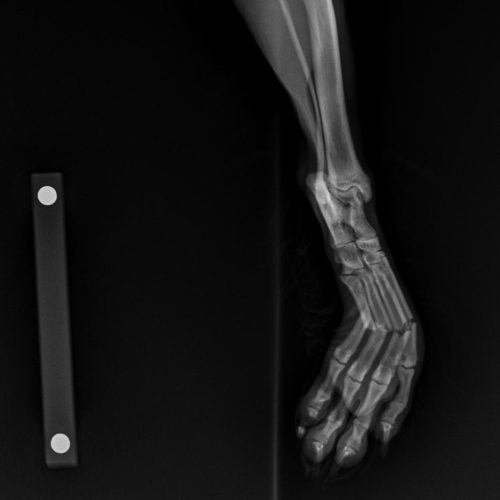

A ortopedia em cães e gatos é uma especialidade veterinária que se dedica ao diagnóstico e tratamento de doenças e lesões do sistema musculoesquelético, que inclui ossos, articulações, músculos e ligamentos. Problemas comuns nessa área incluem fraturas, luxações, displasia coxofemoral da anca e artrite.

Os sinais de problemas ortopédicos podem incluir claudicação, dor, dificuldade para se mover e mudanças no comportamento. O diagnóstico geralmente envolve exames físicos, radiografias e, em alguns casos, ressonância magnética.